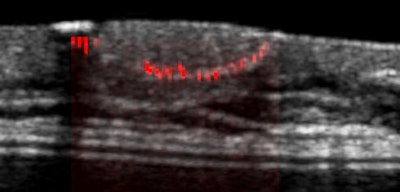

Microcalcifications in a blood vessel in the breast. Image courtesy of UltraVision.Company leaders say the software aims to expand breast cancer detection with ultrasound into physician's offices, mammography centers, and underserved international markets.

The company has filed for a patent on MC-mode, which detects microcalcifications and their locations from their vibration. The company also filed a patent on differentiating between type-1 and type-2 microcalcifications.